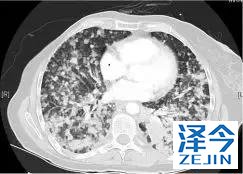

一位77岁的女性患有EPS15-NTRK1 IV期非小细胞肺癌,我们可以看到她的双肺满是病灶,并且出现了肝脏和脑转移,可以说是非常非常晚期了,

肺靶病变达到缓解,我们可以明显的看到前后的图像,病灶明显缩小了,

脑转移病变显示缩小了95%!

初始, 2018年6月 3周期 2018年8月